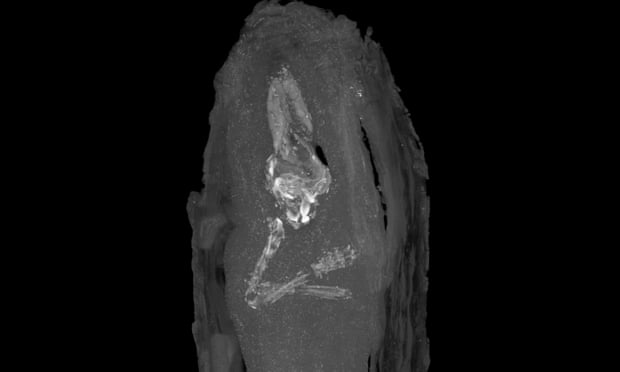

Un pequeño ataúd excavado en Giza en 1907 ha revelado ahora que contiene el ejemplo más joven de un feto humano embalsamado y enterrado en la sociedad del Antiguo Egipto.

Este descubrimiento es el único ejemplar verificado académicamente de feto momificado con tan solo dieciséis a dieciocho semanas de gestación.

El examen utilizando imágenes de rayos X en el Museo Fitzwilliam fue concluyente, y sugirió que podría contener un pequeño esqueleto. Por lo tanto, se decidió escanear con micro CT (tomografía computarizada) el pequeño bulto en el Departamento de Zoología de la Universidad de Cambridge. Las imágenes de cortes transversales dieron las primeras imágenes de los restos de un pequeño cuerpo humano dentro de los envoltorios, los cuales permanecen inalterados.

El análisis de los dedos de las manos y los pies permitió datar con exactitud el periodo de gestación del feto en no más de 18 semanas.